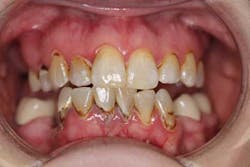

Sara (name changed) was 37 years old when she first walked into my office because of a toothache (figure 1). A review of her health history included: Crohn’s and celiac disease, depression, asthma, and several surgeries; her prescriptions included: antiseizure, depression, insomnia, and OCD (obsessive-compulsive disorder) medications. The cocktail of these drugs were a necessary evil; dry mouth ensued and rampant caries took over. Due to lack of financial resources, instead of restoring her teeth she had them removed one by one, including the tooth she came in about that day (No. 13).

After a complete assessment, it was apparent that Sara’s options were limited with her existing dentition. The caries present were large and apple-cored around the teeth, making the long-term restorative prognosis questionable or guarded at best (figures 2-5). Several key teeth for partial abutments were either missing or grossly carious.